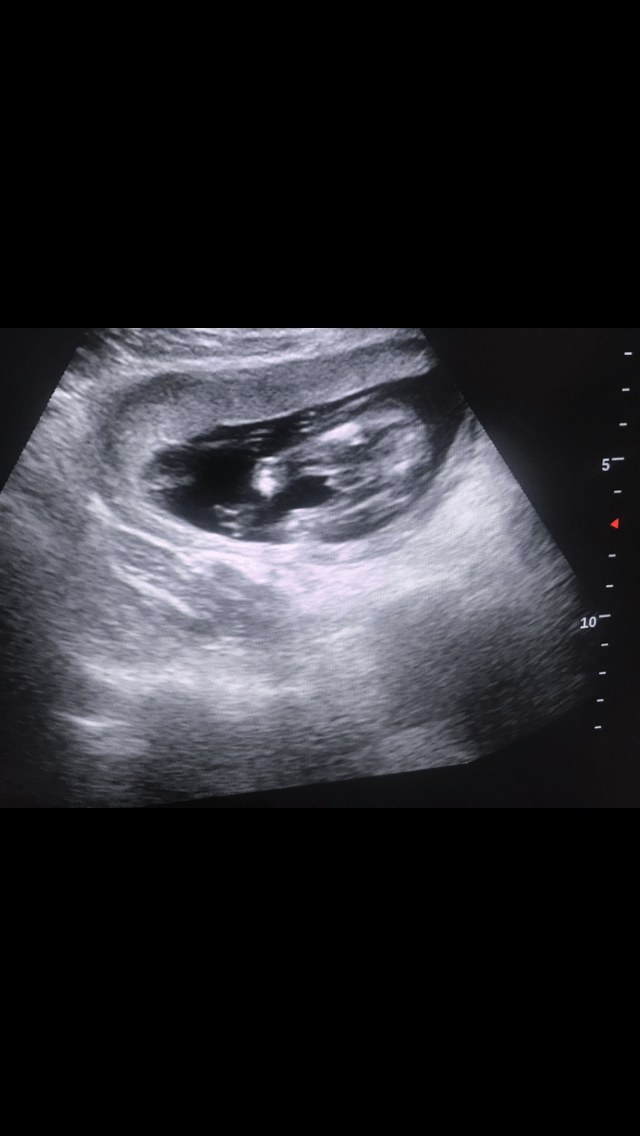

Dziewczyny jestem w 6 miesiącu ciąży. Mam takie jedno zdjęcie z usg gdzie ładnie wszystko widać, niestety do tej pory chodziłam do bardzo kiepskiego ginekologa i powiedział mi ze on nie jest w stanie rozpoznać płci. Moze któraś z mam rozpozna płeć bo widziała to samo. Dołączam zdjęcie z usg. Dziękuje z góry i proszę tylko bez hejtu.

#Tangerieme na początku była dziewczynka, później że chłopiec. A teraz gin stwierdził że zasłania rączka i nie jest pewny :/ I dostałam takie zdjęcie.Dziwne ze w takim czasie ginekolog nie umie określić płci. Mi wydaje się ze chłopak

I się zastanawiam, bo nie wiem czy to roczka czy to penis? I bez tego to mi przypomina bardziej buleczke niż worek mosznowy

Faktycznie ciężko określić niby część wygląda na wargi sromowe bo jest bułeczka z kreseczka po środku ale coś wystaje wyraźnie tyle że to nie wygląda jak rączka a bardziej jak pepowina sama widziałam podobny obraz pani doktor pokazywała mi ,,bułeczke" a ja pytałam tylko co to jest to po środku bo coś wysawało i już chciałam się kłócić że przecież widzę że chłopak bo siusiak wystaje ale pani doktor udowodniła mi że to pepowina bo przepływała krew przez nią i faktycznie zaraz dzidzia zrobiła fikołka pepowina się odsunela i było widać samą bułeczke więc chyba pozostaje ci nadal czekać może na kolejnej wizycie coś lepiej będzie widać gdybym ja miała oceniać to wygląda jak wargi sromowe a to pomiędzy na pepowine ale nie jestem lekarzemCześć Dziewczyny